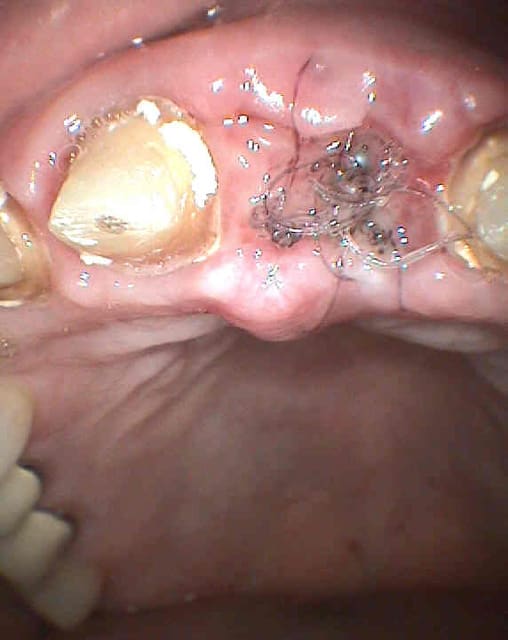

revu ce soir, je n'ai rien déposé, mais après un long examen et beaucoup d'interrogations, j'ai fait l'ouverture de la 13:

-compo volumineux

-douleur exacerbée au froid

-douleur a la palpation en regard de l'apex

-élargissement ligamentaire sur la radio.

pour la 12, il y a une douleur a la mmobilisation, mais radiologiquement, je ne vois rien.

je revois la patiente jeudi:

- si ca va mieux, c'est donc la 13

sinon, je ferais une dépose du tenon fibré sur 12, et examen au microscope opératoire du canal, pour detecter une éventuelle fracture ( la racine est rectiligne, je crois que je devrais y voir clair.

je vous laisse les clichés.

sur les photos, la gauche et la droite sont inversées